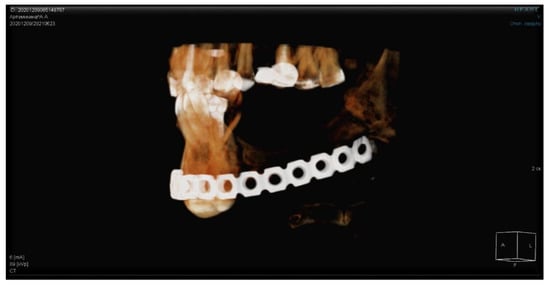

The patients in the main group (43 subjects) underwent segmental resection of the jaw after preoperative preparation (Figure 2 and Figure 3a,b).

An analysis of the results obtained from the Numeric Pain Rating Scale demonstrated that the mean pain intensity before treatment was 8.9 points in the control group, and 9.7 in the main group (Figure 4). These values are indicative of “unbearable pain.” After treatment (30 days), the pain score in the control group decreased and amounted to 4.1; this is evidence of the persistence of “moderate pain” in the patients. In patients who underwent segmental jaw resection (Figure 5a,b and Figure 6), the mean pain intensity was 0.5. There was no relationship with gender, but there was a direct relationship between the intensity of the pain and the stage of the process (CI = 95%).

Table 3 presents the results obtained with the Visual Analog Scale in patients with MRONJ after six months, which make it possible to assess changes in this parameter over time. After treatment, this parameter value was 3.6 in the control group and 0.1 in the main group (Figure 7a–d).

In the patients in the main and control groups, the pain intensity index values before treatment approached similar values. After surgery, the pain intensity index in the main group was close to normal values. In the control group, 30 days after conservative treatment, there was a tendency for the parameter to decrease; however, after six months, it did not reach the “no pain” mark (Figure 8 and Figure 9a,b).

Figure 1. (ad) Patient A: 47-year-old female. DS: Medication-related osteonecrosis of the jaw (the left side). Surgical treatment: Resection of the lower jaw on the left (9 September 2018).

Figure 9. (a,b) Results after five years.